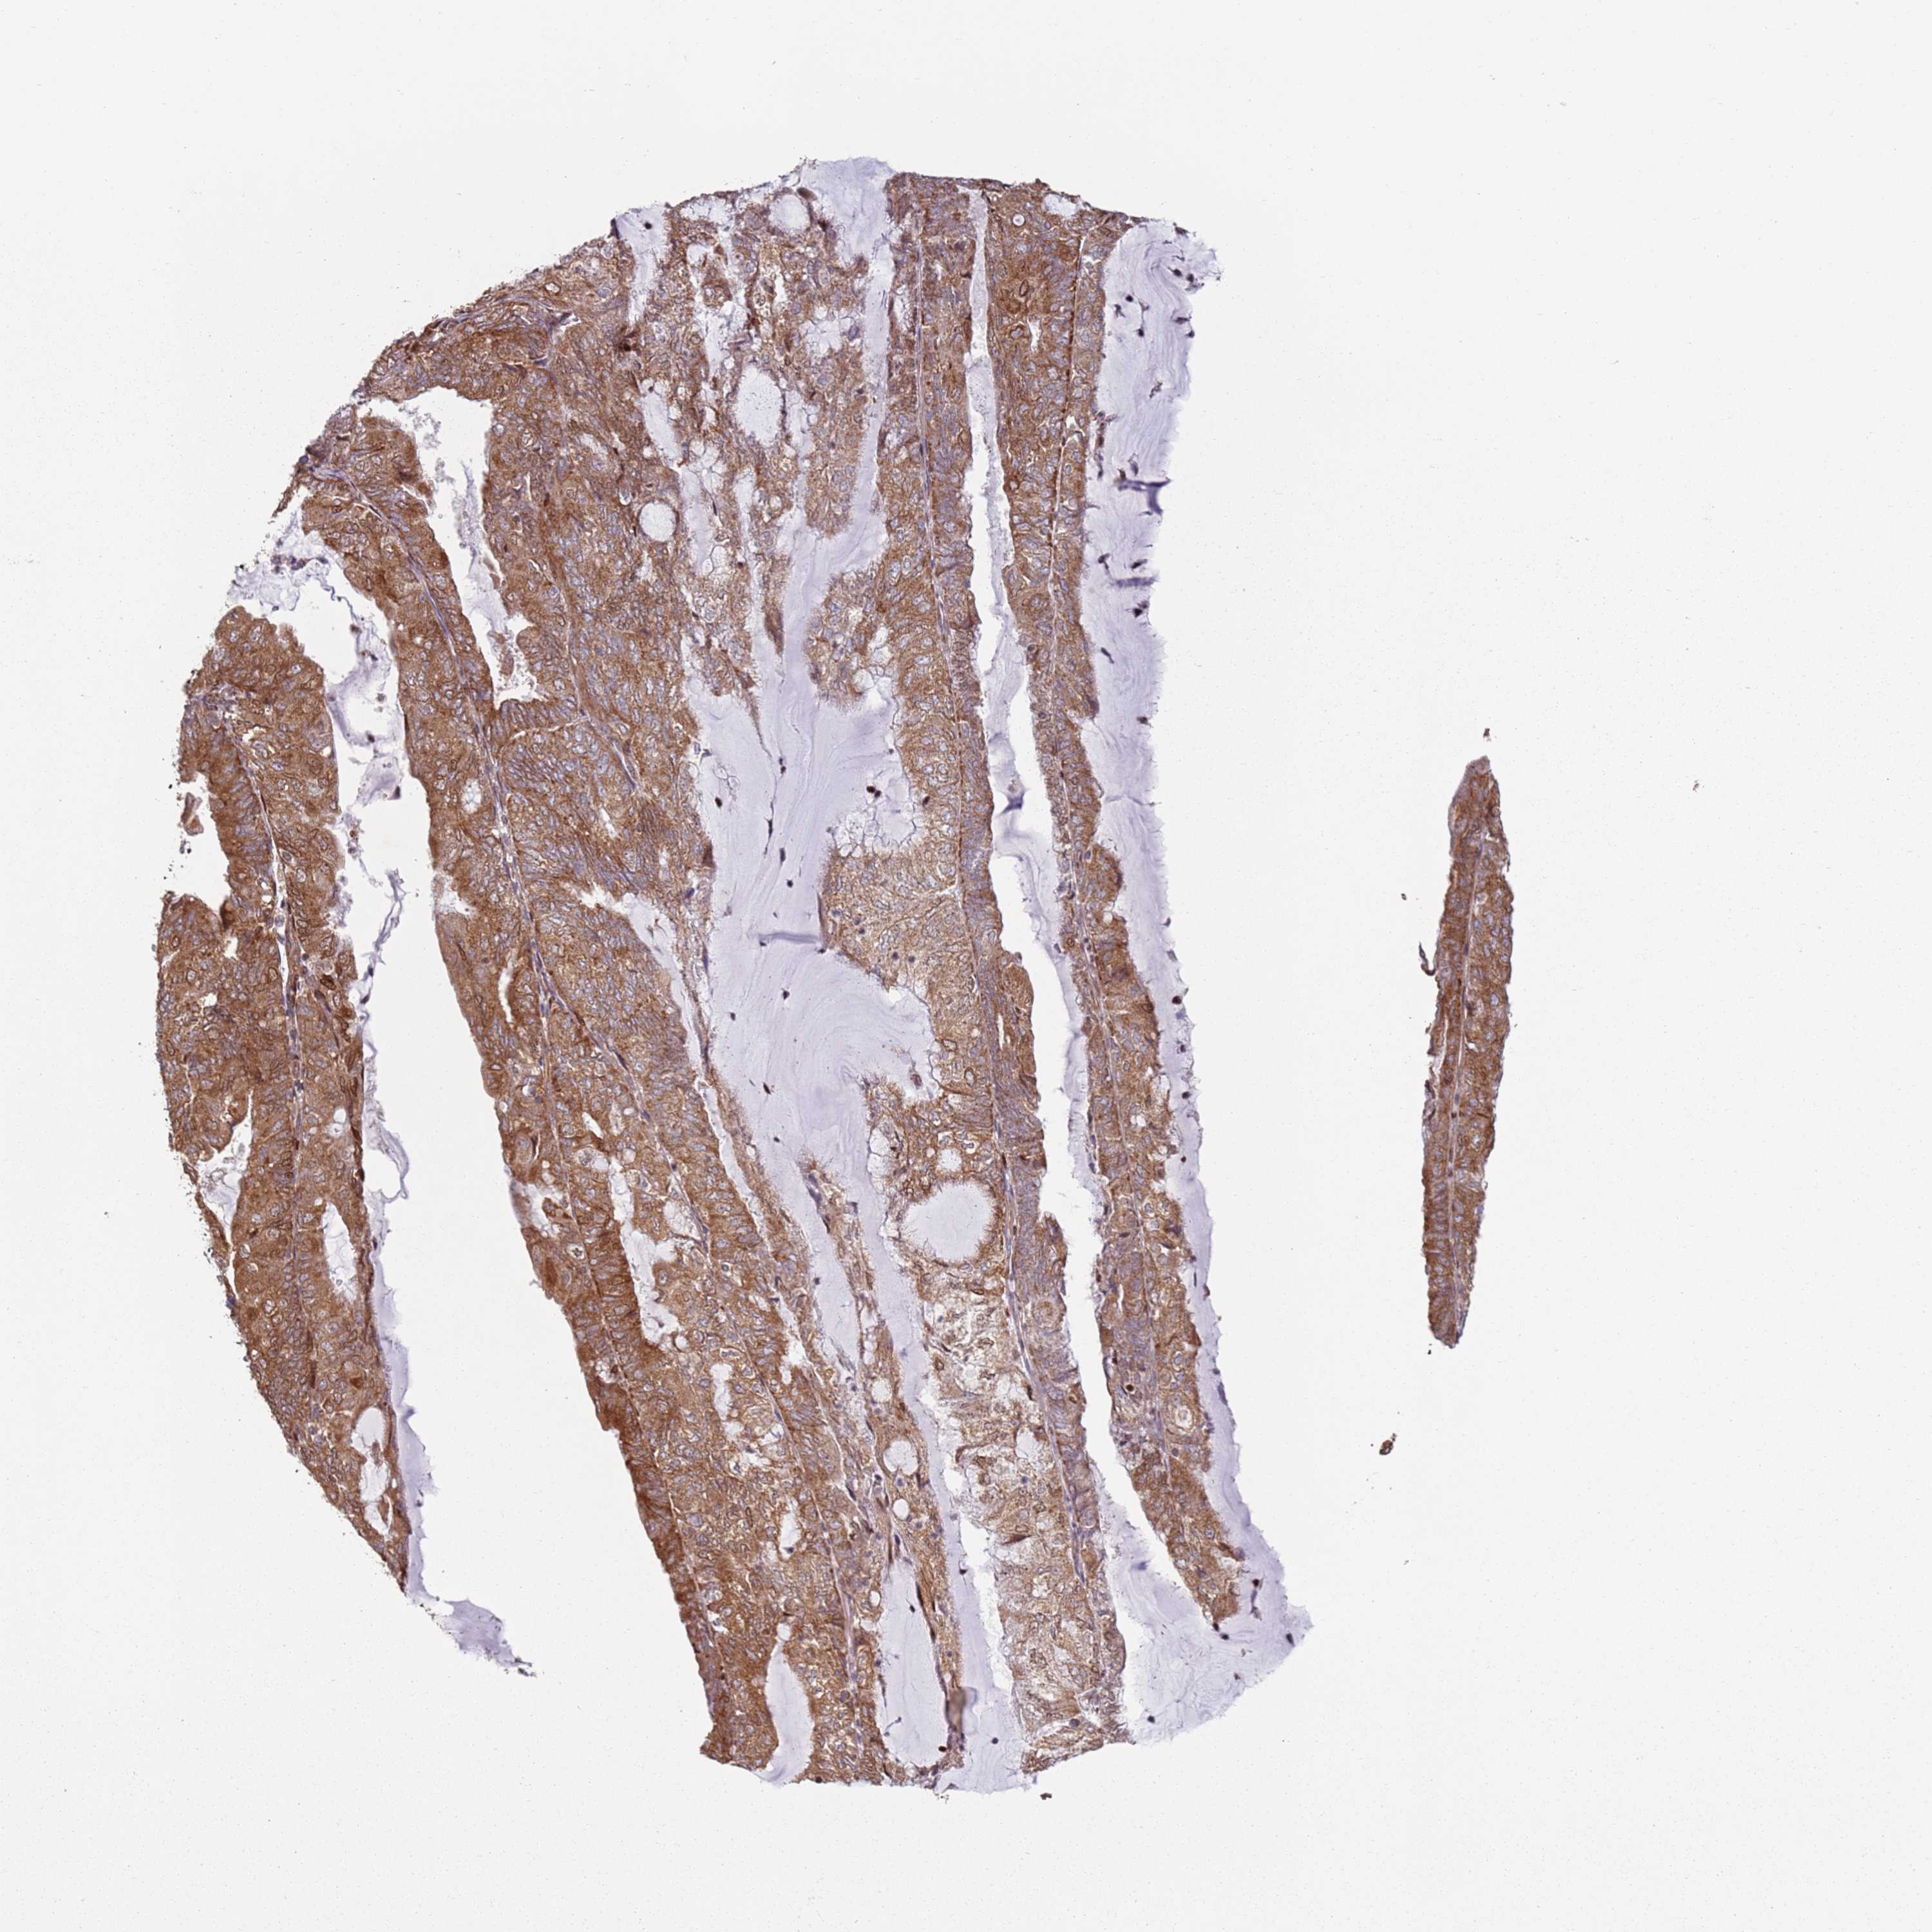

ENDOMETRIAL CANCER - Protein expressioni

A mouse-over function shows sample information and annotation data. Click on an image to view it in a full screen mode. Samples can be filtered based on level of antibody staining by selecting one or several of the following categories: high, medium, low and not detected. The assay and annotation is described here.

Note that samples used for immunohistochemistry by the Human Protein Atlas do not correspond to samples in the TCGA dataset.

Antibody stainingi

Antibody staining in the annotated cell types in the current human tissue is reported as not detected, low, medium, or high, based on conventional immunohistochemistry profiling in selected tissues. This score is based on the combination of the staining intensity and fraction of stained cells.

Each image is clickable and will lead to virtual microscopy that enables deeper exploration of all samples and also displays staining intensity scores, fraction scores and subcellular localization as well as patient and tissue information for each sample.

Antibody HPA046084

Staining

High

Medium

Low

Not detected

Intensity

Strong

Moderate

Weak

Negative

Quantity

>75%

75%-25%

<25%

None

Location

Nuclear

Cytoplasmic/membranous

Cytoplasmic/membranous,nuclear

Adenocarcinoma, NOS